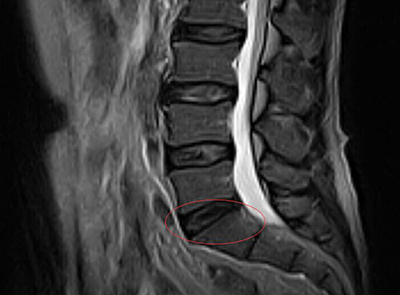

2015年6月22日,张先生来到我院治疗,门诊进行MRI检查显示:“1、腰椎退行性变;2、L2/3,L3/4,L4/5椎间盘膨隆;3、L5/S1椎间盘后缘突出”,拟“椎间盘源性腰痛”收入我院。

MRI影像图